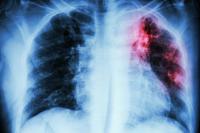

A quarter-century ago, researchers discovered that cystic fibrosis is caused by mutations in the CFTR gene, which makes an eponymous protein that transports chloride ions in and out of the cell. Without ion transport, mucus in the lung becomes thicker and stickier and traps bacteria—especially Pseudomonas—in the lung. The trapped bacteria exacerbate the body’s inflammatory response, leading to persistent, debilitating infections.